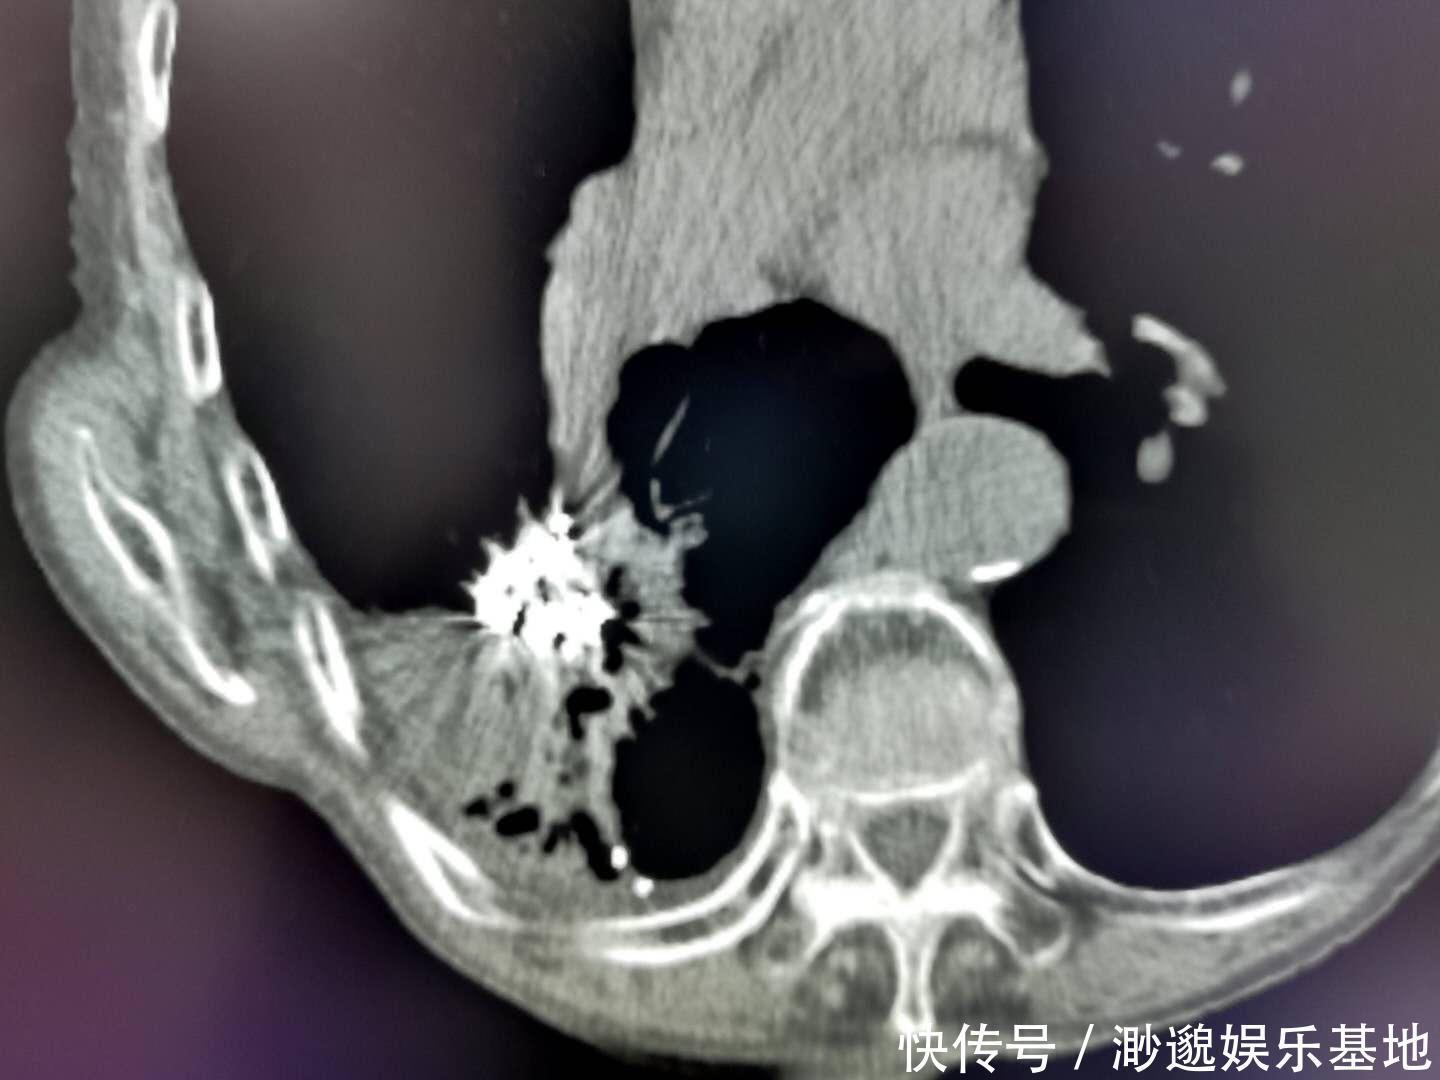

这是一位80多岁的老爷子,查出右侧肺鳞癌,年纪太大不能耐受手术,选择放射性粒子植入,用辐射杀灭癌细胞,已经三年多了,老爷子至今病情稳定(白色部分为放射性粒子,CT片上呈金属密度,很亮):